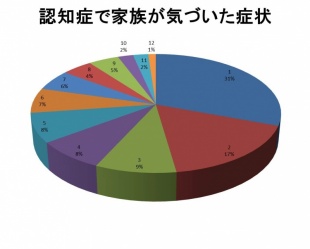

ご家族のアンケートです。最初どのような症状で「認知症かも?」と思いましたか?

□1.物忘れがひどい

□2.ささいなことで怒り出す

□3.道に迷うことがある

□4.落ち着きがない、機嫌が悪いことが多い

□5.気持ちが沈む、あるいは周囲に関心を示さない

□6.歩きまわるなど目的のわからない行動が目立つ

□7.ささいなことを心配したり怖れたりする

□8.会話がうまくできなくなった

□9.「誰かに物を盗まれた」という

□10.着替えがスムーズにできない

□11.呼びかけに反応しないことがある

□12.夜眠らず、家の中を歩きまわる

認知症がある場合、通常は家族が症状の変化に気づいて病院に受診されることがほとんどです。

当院に受診された認知症のある30人の方のデータです。「物忘れがひどくなった」「ささいなことで怒り出す」「道に迷うことがある」がよく家族に気づかれる症状です。

以下のグラフがデータをまとめたものです。